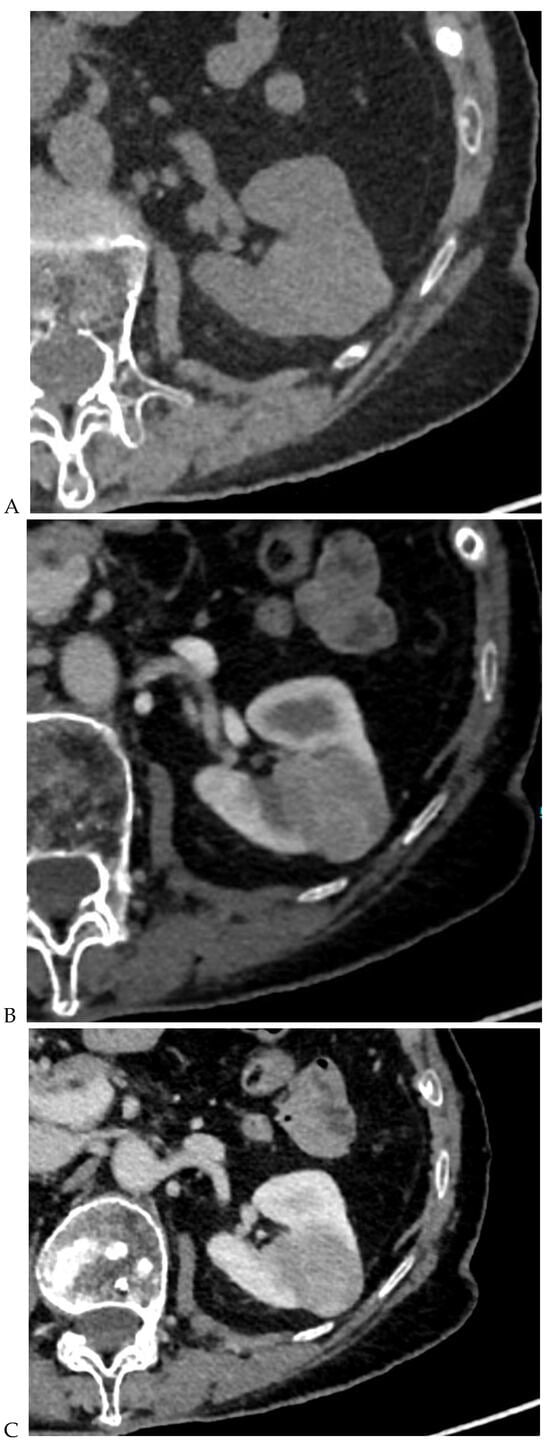

Figure 4.

Multiphasic CT enhancement of a papillary renal cell carcinoma in the middle part of the right kidney of a 63-year-old woman. (A) Mean unenhanced attenuation was 35 HU. (B) Mean corticomedullary phase attenuation was 45 HU. (C) Mean nephrographic phase attenuation was 59 HU. (D) Mean excretory phase attenuation was 65 HU.